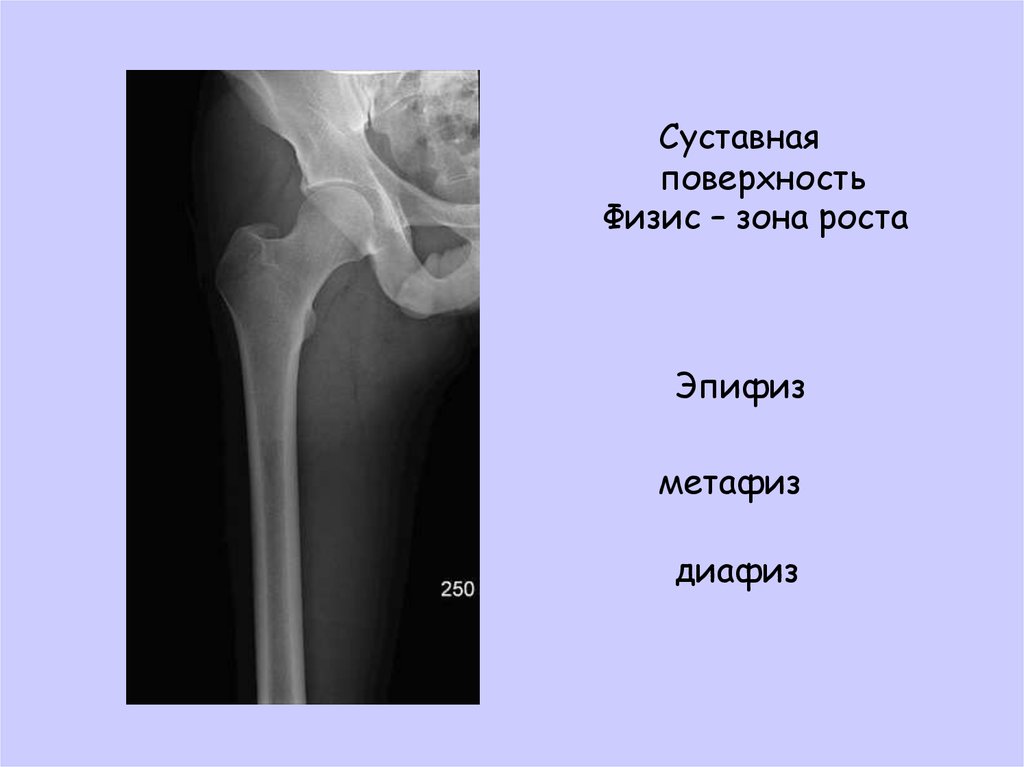

Физис это

Физис это 116 фото